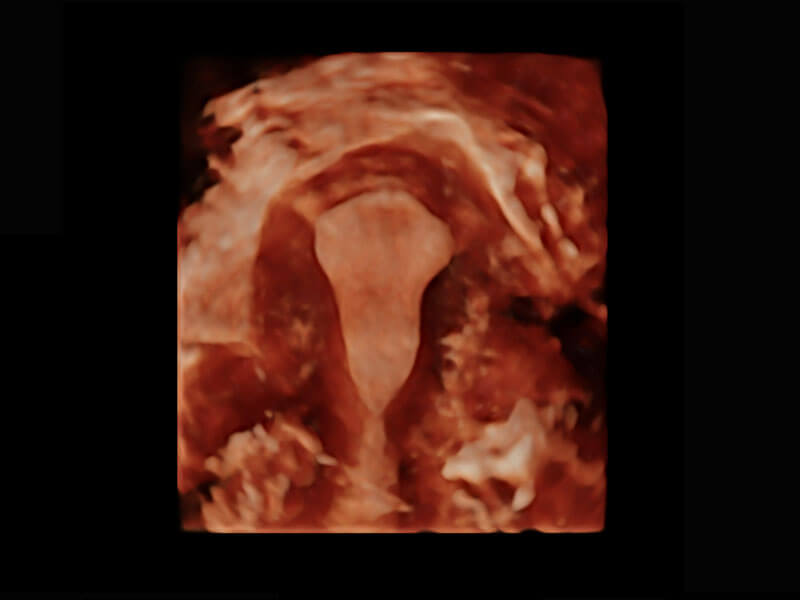

生殖健康

P60优异的图像质量搭载专科探头,在妇科基础疾病的诊断、卵泡生长的监测、输卵管通畅情况的判别等方面为您提供生殖应用方案。

• 腔内三维-宫内节育器